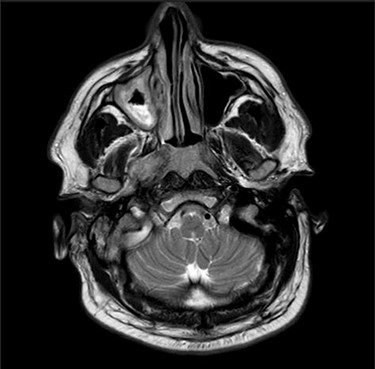

Computerized tomography (CT) of the internal meatuses demonstrated soft tissue thickening of the right middle ear cavity, aditus, antrum and mastoid air cells in keeping with otomastoiditis (Fig. 1), but no destructive or erosive pathology to account for the multiple neuropathies elicited on examination. A subsequent magnetic resonance imaging (MRI) scan demonstrated a 2.5 centimeter (cm) right skull base inflammatory mass, involving the internal carotid artery and jugular foramen (Fig. 2). Anti-microbial therapy was subsequently changed to intravenous meropenem and topical ciprofloxacin ear drops. The patient underwent a right cortical mastoidectomy and grommet insertion at Day 5, with well-pneumatized air cells and inflammatory tissue observed within the aditus.

Axial MRI image showing high attenuation lesion affecting the right skull base.